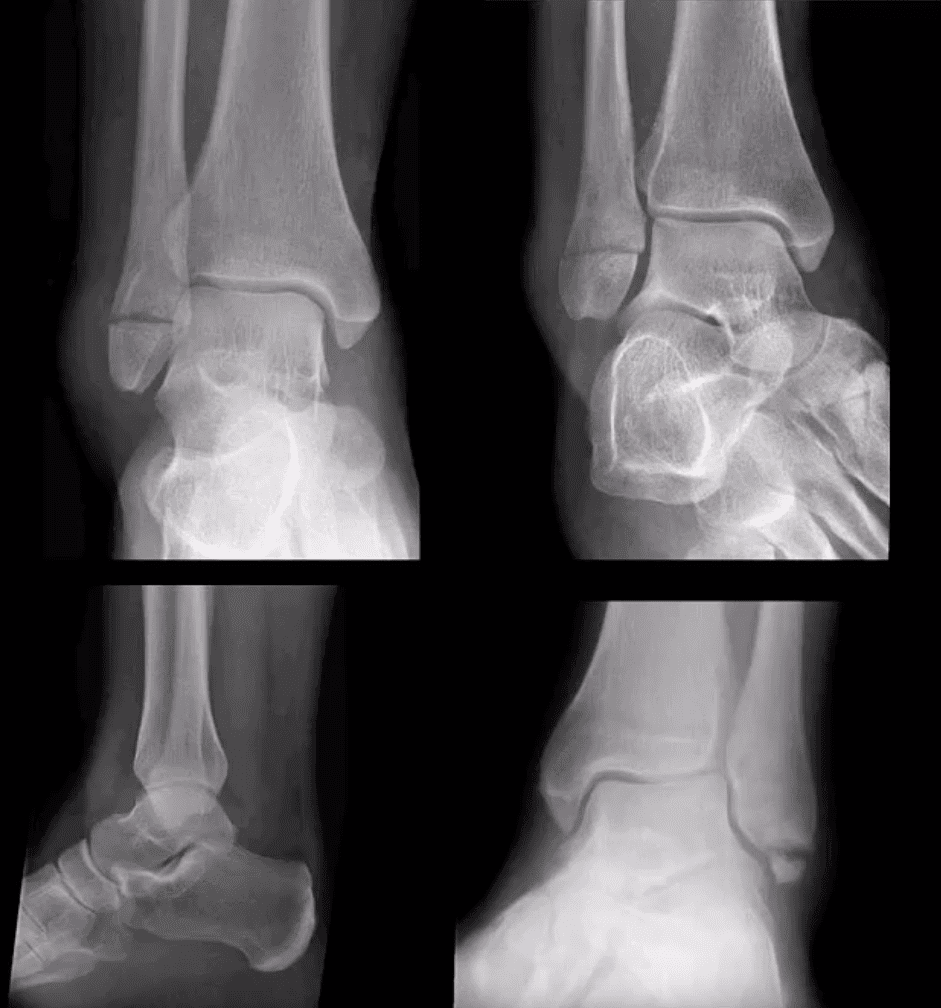

Bimalleolar & Trimalleolar Fx

- Above top images Bimalleolar Fx v. unstable, result of pronation and abduction/external rotation. Rx: ORIF.

- Trimalleolar Fx: 3-parts ankle Fx. Medial and lateral malleolus and avulsion of theposterior aspect of tibial plafond. More unstable. Rx: operative